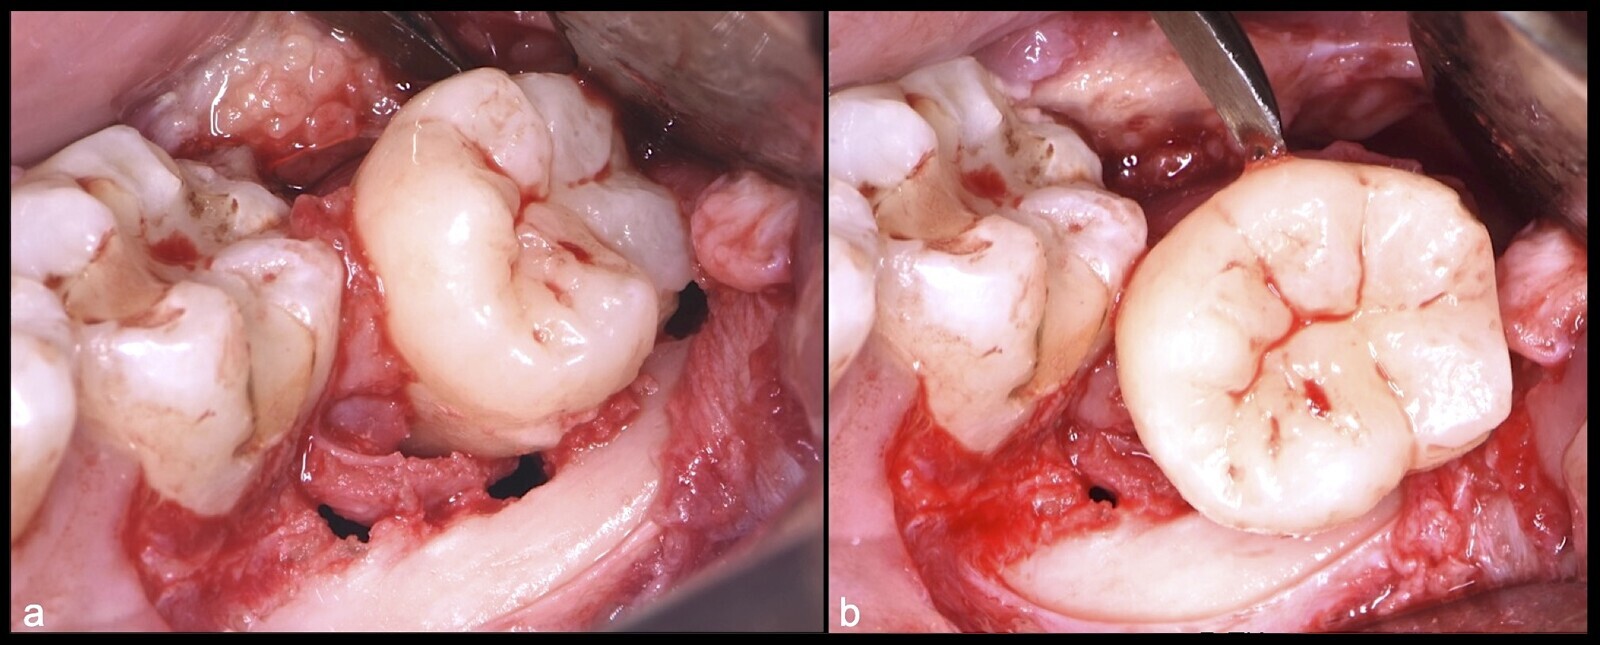

Paciente de sexo femenino con 34 años, acude a consulta por molestia en la zona 38. Clínicamente se observa zona edematizada, sintomática a la palpación. Presenta apertura ligeramente limitada, crepitación unilateral en ATM (articulación temporomandibular) derecha, asintomática a la apertura o cierre articular. En el examen imagenológico se confirma impactación dental con posible compromiso distal de la pieza 37. Pieza 38 en relación IIIC (Pell-Gregory,1993) y posición mesioangulada (Winter, 1926) con aparente formación incompleta de raíces.

Figura 21. Ampliación de la ventana ósea con el inserto plano de corte de punta aserrada (a). Extirpación de tejido blando remanente con inserto de corte y coagulación del electro bisturí (b). Exposición de la corona clínica de la pieza 3.8 (c).

Figura 22. Ampliación de ventana ósea distal con inserto plano de corte de punta aserrada (a). Desplazamiento distal de pieza 38 con botador recto convencional (b).

Figura 23. Luxación de pieza 3.8 con botador recto convencional (a). Extracción de pieza 3.8 (b).